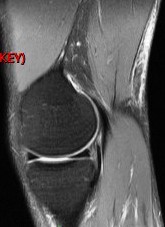

Figure 3 for case Semitendinosus tendon tear, retracted( RID2717 )

Figure 3